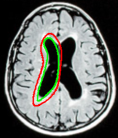

Refer to captionRefer to captionRefer to captionRefer to captionRefer to captionRefer to captionRefer to captionRefer to captionRefer to captionRefer to captionRefer to captionRefer to captionRefer to captionRefer to captionRefer to captionRefer to captionRefer to captionRefer to captionRefer to captionRefer to captionRefer to captionRefer to captionRefer to captionRefer to captionRefer to captionRefer to captionRefer to captionRefer to captionRefer to captionRefer to captionRefer to captionRefer to captionRefer to captionRefer to captionRefer to captionRefer to caption\begin{array}[]{cccccc}\includegraphics[width=72.26999pt]{Optimal-inti.pdf}&\includegraphics[width=72.26999pt]{Optimal-final.pdf}&\includegraphics[width=72.26999pt]{40.pdf}&\includegraphics[width=72.26999pt]{OAS1_0040_msp_niiSeg.pdf}&\includegraphics[width=72.26999pt]{140.pdf}&\includegraphics[width=72.26999pt]{OAS1_0140_msp_niiSeg.pdf}\\ \includegraphics[width=72.26999pt]{157.pdf}&\includegraphics[width=72.26999pt]{OAS1_0157_msp_niiSeg.pdf}&\includegraphics[width=72.26999pt]{168.pdf}&\includegraphics[width=72.26999pt]{OAS1_0168_msp_niiSeg.pdf}&\includegraphics[width=72.26999pt]{221.pdf}&\includegraphics[width=72.26999pt]{OAS1_0221_msp_niiSeg.pdf}\\ \includegraphics[width=72.26999pt]{237.pdf}&\includegraphics[width=72.26999pt]{OAS1_0237_msp_niiSeg.pdf}&\includegraphics[width=72.26999pt]{293.pdf}&\includegraphics[width=72.26999pt]{OAS1_0293_msp_niiSeg.pdf}&\includegraphics[width=72.26999pt]{395.pdf}&\includegraphics[width=72.26999pt]{OAS1_0395_msp_niiSeg.pdf}\\ \end{array}

Figure 12: Segmentation of corpus callosum images in sagittal plane T1-weighted brain magnetic resonance images taken from [37]. For all images, the same template was used and initialized in a manner similar to the way shown in the top left corner image. The converged results using the proposed shape template approach and the result obtained on subsequent refinement using snake energies[22] are displayed alongside.

In Figure 12, we show the results obtained for segmentation of corpus callosum in T1-weighted MR images. Many techniques on segmentation of corpus callosum are affected by the adjoining fornix structure due to the similarity in intensities. However, it can be observed from the results that the proposed snake is less affected by the fornix. We further refine results obtained using the proposed technique with gradient energies[22]. We display the results obtained on refinement alongside the output from the proposed shape-based approach.